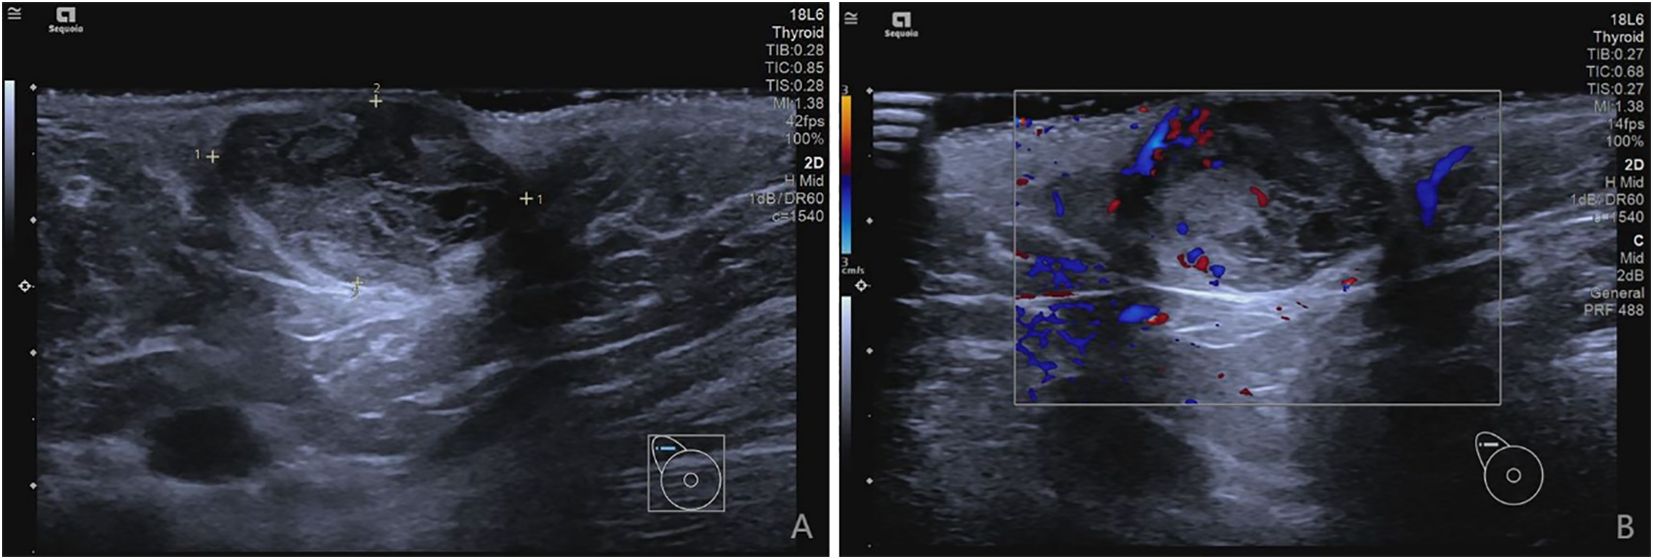

On current physical examination, we identified a well-circumscribed, smooth-surfaced, mobile mass (2.5×1×1 cm) elevated above the skin in the right axilla. The lesion showed no ulceration, vesicle formation, erythema, edema, or peau d’orange sign. No vascular bruits were auscultated. Examination of both breasts revealed no abnormalities. Ultrasonography demonstrated a solid hypoechoic mass (29.3 mm × 13.7 mm × 16.2 mm) located 9 mm beneath the epidermal surface in the right axilla. The lesion exhibited well-defined margins, regular morphology, and heterogeneous internal echogenicity. Color Doppler flow imaging (CDFI) revealed moderately abundant intralesional vascularity (Figures 1A, B). Preoperative abdominal ultrasonography and chest radiography revealed no detectable abnormalities.

Figure 1. (A, B) demonstrate ultrasonographic findings of a solid hypoechoic nodule in the right axilla.